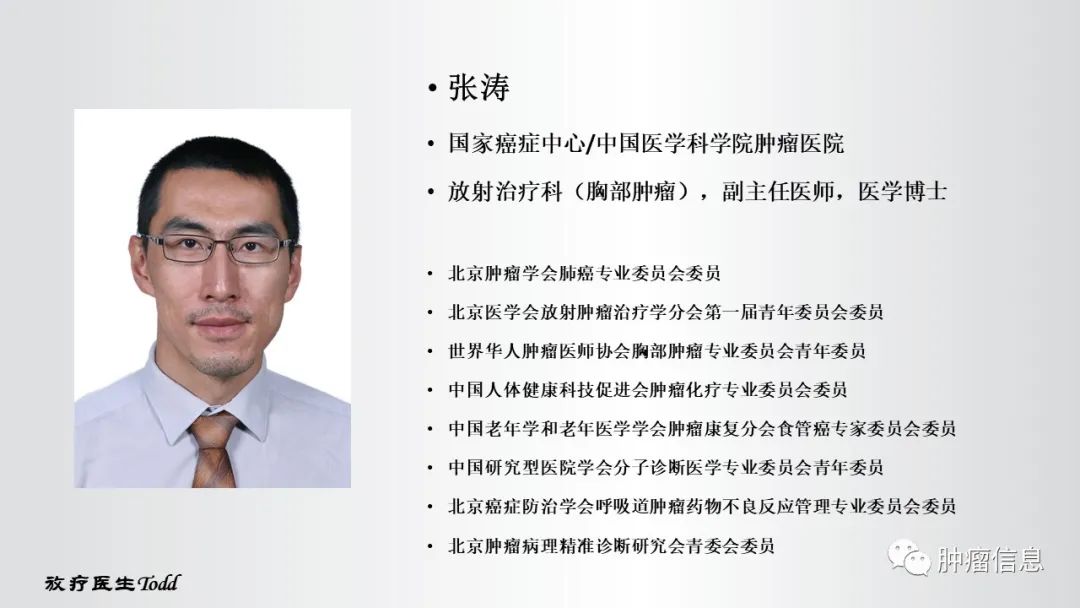

作者信息

说明:本文转自肿瘤信息,原作者张涛,版权归原作者所有,如有侵权,请联系删除。